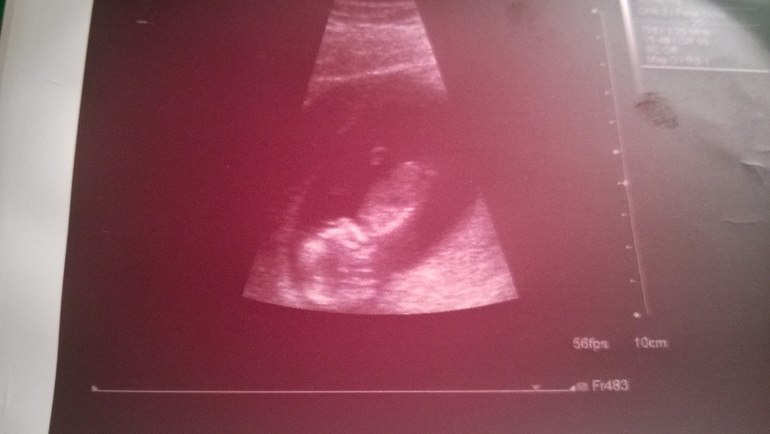

УЗИ, КТГ, доплерДевочки, со вчерашнего дня пребываю в почти парящем счастливом состояние - мы с мужем впервые видели и слышали нашего малыша

На 22 число было назначено наше первое плановое УЗИ, конечно взяла с собой любимого, хотелось, чтобы сам увидел все. И вот вчера на большущем экране наблюдали как наше чудо поворачивается, прыгает и машет нам ручкой, слушали биение сердечка, даже не вериться, что такое манюсенькое сердечко может так громко и сильно стучать...

конечно, были слезы радости и умиления, сложно сдержать себя... да, я знала, что во мне новая жизнь, что там зарождается и растет наше маленькое чудо. но одно дело знать, но совсем другое - увидеть, осознать, наблюдать как он шевелиться, как поднимает ручки, как поворачивается, когда поворачиваюсь я. это не счастье, это - СЧАСТЬЕ, это не передать словами, но я уверена, что вы меня понимаете )))